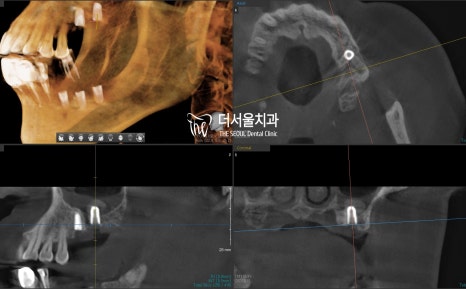

본격적으로 식립을 하기에 앞서,

골질과 골양, 주변 조직과의 관계를 확인했습니다.

이후 총 5곳에 implant fixture를 심은 다음

잇몸 형성에 도움을 줄 healing abutment까지 체결을 도왔습니다.

연결 이음새 부분이 매끄럽게 잘 이어지고 있는 모습이네요.

식립 후 CT